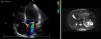

2A) RM abdominal axial. Tumoración quística heterogénea en riñón izquierdo, de 7,6×6,2cm de diámetro.

2B) RM cerebral. Lesiones hipercaptantes, situadas en el hemisferio cerebeloso izquierdo, una de unos 5mm y la otra más periférica de 3mm, que corresponden a pequeños hemangioblastomas cerebelosos.

Estos resultados indican la presencia de feocromocitoma y justifican el cuadro clínico. Con este diagnóstico de sospecha en contexto de síndrome de von Hippel Lindau, la paciente pasa a cargo de Servicio de Endocrinología. Se completa el estudio solicitándose RM abdominal y RM cerebral. En la primera, se objetiva una masa suprarrenal izquierda de 2,3cm de diámetro bien delimitada sugestiva de feocromocitoma (fig. 1B). Del mismo modo se informa de una tumoración quística heterogénea en riñón izquierdo, de 7,6×6,2cm de diámetro, en la glándula pancreática se aprecian numerosas formaciones con señal quística tanto en cabeza, cuello como en cola (fig. 2A). La RM cerebral muestra dos pequeñas lesiones hipercaptantes, situadas en el hemisferio cerebeloso izquierdo, una de unos 5mm y la otra más periférica de 3mm, que corresponden a hemangioblastomas cerebelosos (fig. 2B). Una vez realizado el diagnóstico de imagen se contacta con servicio de Urología para planear el abordaje quirúrgico. Se inicia la preparación preoperatoria con dosis crecientes de fenoxibenzamina hasta alcanzar los 20mg/12h. Posteriormente, la paciente presenta un cuadro de palpitaciones, objetivándose taquicardia sinusal que se controla con propranolol a dosis de 20mg/12h. Una vez alcanzada la estabilidad clínica se decide la intervención quirúrgica. Es intervenida 20 días después practicándose una nefrectomía radical y suprarrenalectomia por vía laparoscópica. La paciente no presenta complicaciones inmediatas, objetivándose una mejoría de las cifras tensionales, así como de las palpitaciones. El estudio anatomopatológico mostró un feocromocitoma y un carcinoma renal de células claras. Se solicita un estudio bioquímico posquirúrgico en el que se objetivó la normalización de las catecolaminas y metranefrinas en orina. Destacar que la paciente no presenta antecedentes familiares y que el análisis genético mediante MLPA (Multiplex Ligation-dependent Probe Amplification) de ADN leucocitatrio mostró que la paciente es portadora de una deleción del exon 3 del gen VHL en heterocigosis, no existiendo dudas sobre su predisposición al síndrome de VHL. Se concluye, dado que los familiares no están afectos, que es una mutación de novo. Posteriormente ingresó en Neurología por hipoestesia en hemicuerpo derecho siendo diagnosticada de hemangioblastoma intramedular (febrero 2011), en seguimiento por neurocirugía. Actualmente, la paciente se encuentra asintomática desde el punto de vista cardiovascular realizándose ecocardiografía de control en la que se objetiva ausencia de insuficiencia mitral y FEVI normal.